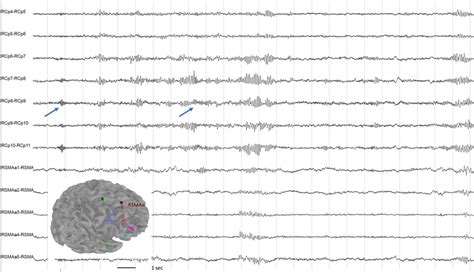

The 21-channel EEG refers to an EEG system that employs 21 electrodes strategically placed on the scalp according to the 10-20 system of electrode placement. This system ensures standardized and reproducible electrode positions across different individuals and laboratories. The 10-20 system is based on anatomical landmarks of the head, with electrodes placed at 10% and 20% intervals of the total front-back and left-right distances of the skull.

Each electrode measures the electrical potential difference between that location and a reference point, typically the ears or a point on the head. These measurements reflect the summed activity of neuronal populations beneath the electrode. The 21 channels provide a comprehensive spatial sampling of the brain’s electrical activity, allowing clinicians and researchers to identify patterns associated with various brain states and conditions. This approach allows for a broad, yet detailed, assessment of brain activity, making it a valuable tool in clinical and research settings.